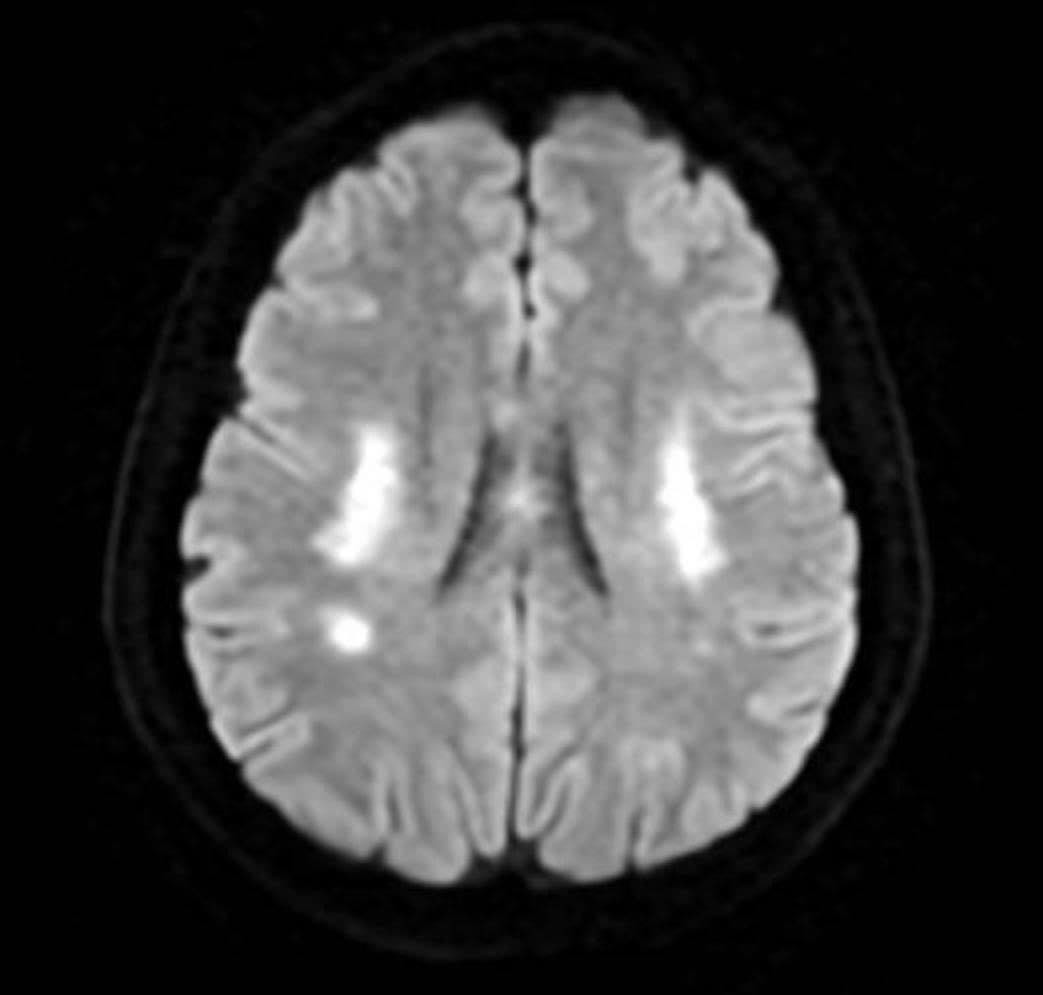

Hình ảnh kiểm tra mạch máu não của người bệnh không ghi nhận tình trạng tắc hoặc hẹp các mạch máu lớn (ảnh: BSCC)

PGS Huy Thắng cho biết, ngay khi nhập viện, người bệnh được chụp MRI não. Hình ảnh cho thấy tổn thương não xảy ra ở hai bên trung tâm bán bầu dục và vùng lồi thể chai. Các thăm dò mạch máu não không ghi nhận tình trạng tắc hay hẹp các động mạch lớn. Dựa trên lâm sàng và hình ảnh học, các bác sĩ chẩn đoán bệnh nhân bị nhồi máu não cấp vùng trung tâm bán bầu dục hai bên và lồi thể chai.